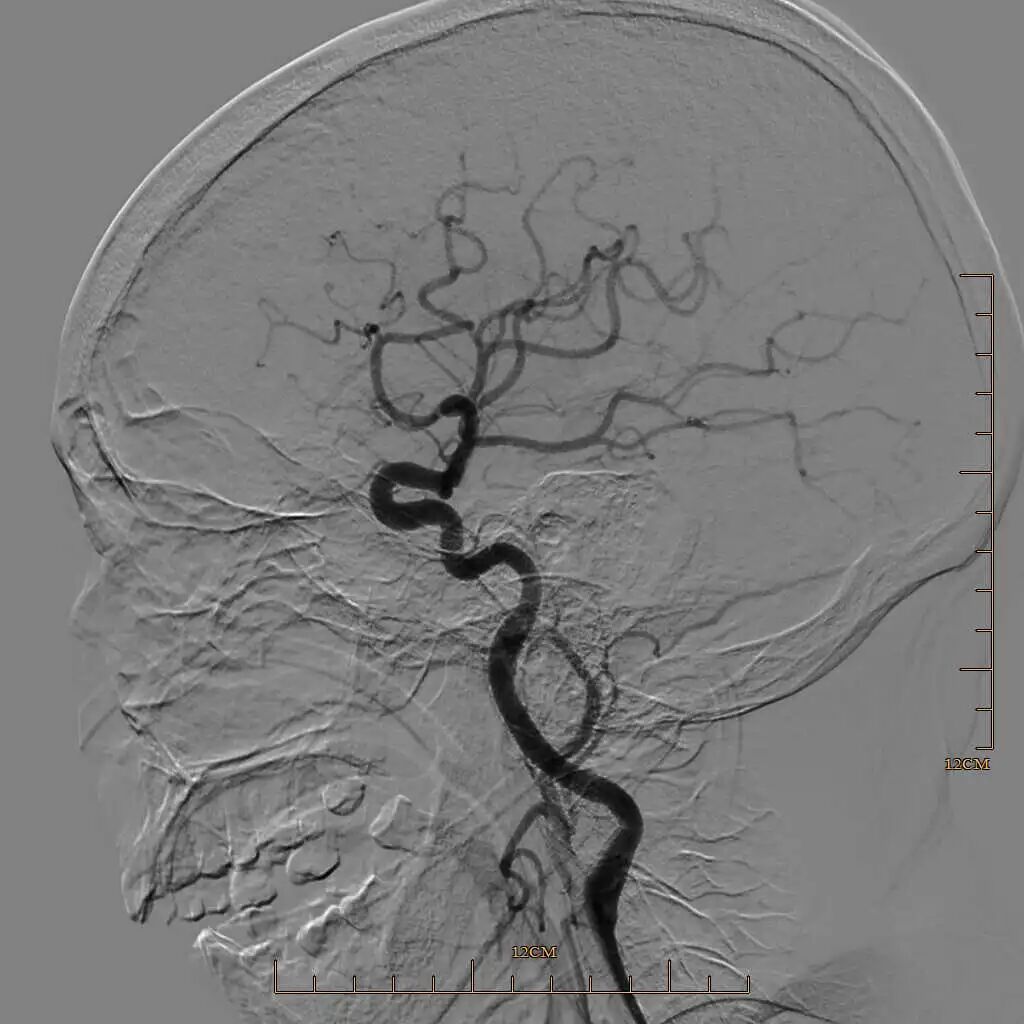

半回收取栓支架取栓后大脑中动脉上干血管再通。

动脉长鞘怎么置入有励可说|Locaste 088励楷长鞘及Tarvos微导丝在左侧大脑中动脉闭塞取栓术中的应用_https://www.jmylbn.com_新闻资讯_第18张

动脉长鞘怎么置入有励可说|Locaste 088励楷长鞘及Tarvos微导丝在左侧大脑中动脉闭塞取栓术中的应用_https://www.jmylbn.com_新闻资讯_第19张

动脉长鞘怎么置入有励可说|Locaste 088励楷长鞘及Tarvos微导丝在左侧大脑中动脉闭塞取栓术中的应用_https://www.jmylbn.com_新闻资讯_第20张

动脉长鞘怎么置入有励可说|Locaste 088励楷长鞘及Tarvos微导丝在左侧大脑中动脉闭塞取栓术中的应用_https://www.jmylbn.com_新闻资讯_第21张